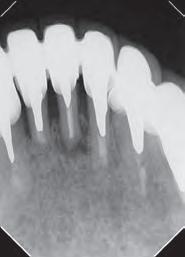

Paciente del género femenino, 44 años de edad, asistió al consultorio para realizar el retratamiento endodóntico del diente 22. Hemos hecho la radiografía inicial para evaluar el diente 22 y nos encontramos con una imagen radiolúcida en forma de globo, caracterizando una reabsorción radicular interna en el diente 21. Hemos hecho, entonces, una nueva radiografía para evaluar el diente 21 (Figura 1).

Figura 1 - Radiografia inicial